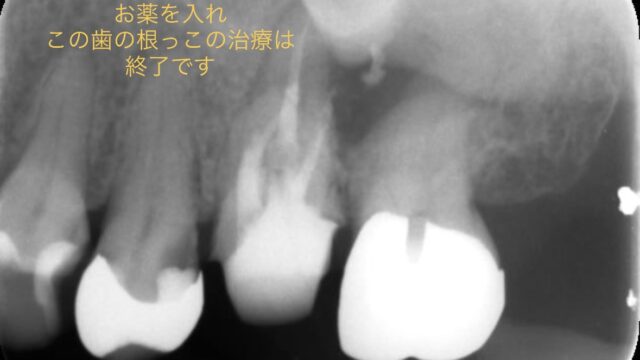

今回の根管治療開始から終了までのデンタルになります。

もし、何度も根管治療をしているのに